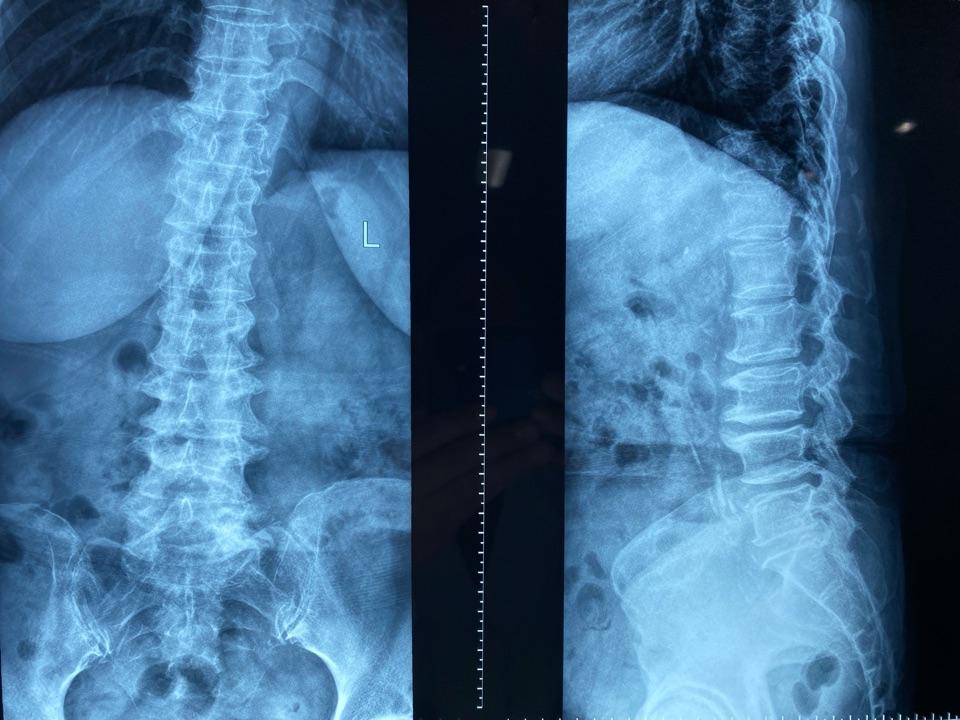

腰椎X线片示:脊柱侧弯,腰椎骨质增生严重